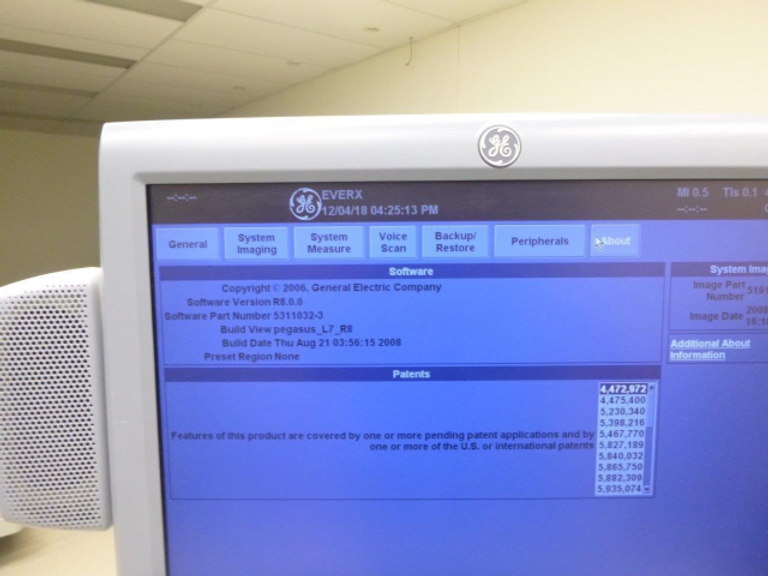

The GE Logiq 7 ultrasound machine stands as a pinnacle of versatility and reliability, catering to a myriad of clinical needs while delivering exceptional imaging quality through cutting-edge 3D technology and an array of enhanced imaging features.

- Advanced Imaging Capabilities: Experience unparalleled image clarity and precision with the Logiq 7’s 3D technology and a comprehensive suite of imaging features, including Power Doppler Imaging, M-Mode, and Color Flow Mode (CFM).

- Seamless Data Management: Benefit from convenient image archiving options, including storage to CD, MOD, or hard drive, enabling efficient data management and access to diagnostic records.